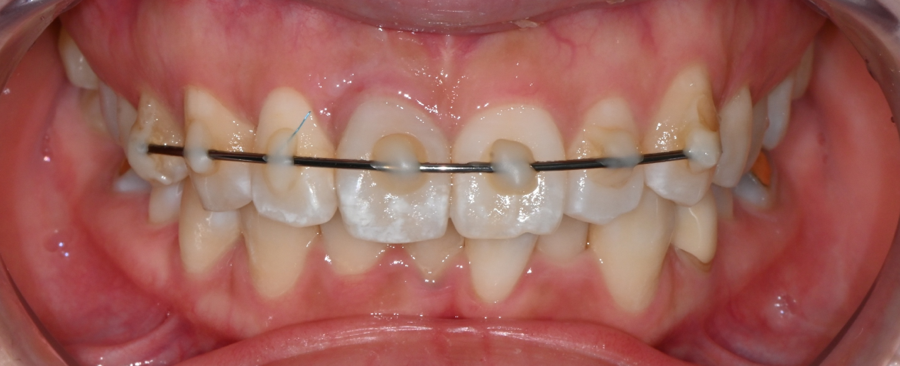

교통사고 충격으로 앞니가 완전히 빠진 상태로

내원하신 환자분의 엑스레이입니다.

치아를 지지하는 잇몸과 주변 구조를 안정시키기 위해

와이어를 이용한 임시 고정 치료를 먼저 진행한 사례입니다.